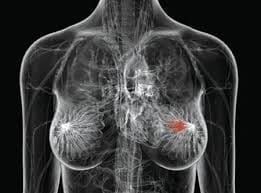

Siamo il centro di riferimento a Catania per la diagnostica senologica di alta qualità. La Mammografia è l'esame di screening per eccellenza, fondamentale per la diagnosi precoce del tumore al seno, in grado di individuare alterazioni anche di dimensioni minime. Presso la nostra struttura, utilizziamo solo tecnologie di ultima generazione per la Mammografia Digitale, garantendo immagini estremamente dettagliate e un'esposizione radiologica ottimizzata. Affidarsi a Servizi Diagnostici Integrati a Catania significa scegliere un percorso di prevenzione serio, gestito con professionalità e sensibilità.

Mammografia Digitale rappresenta oggi lo standard più avanzato nella diagnostica senologica, avendo quasi completamente sostituito la vecchia mammografia analogica. L'evoluzione più significativa è rappresentata dalla

Tomosintesi 3D, una tecnica disponibile presso il nostro centro di

Catania che permette di acquisire immagini della mammella a strati sottili. Questo elimina il problema della sovrapposizione dei tessuti, migliorando significativamente l'individuazione di piccole lesioni, specialmente in seni densi, e riducendo il numero di falsi positivi. Utilizzare la